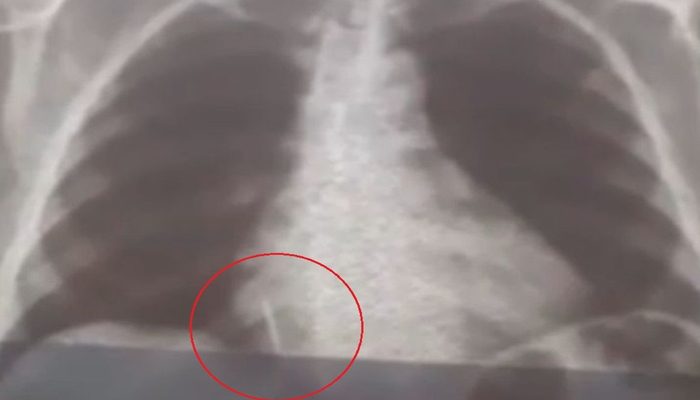

VIXE! Broca de dentista se solta durante atendimento e vai parar dentro de pulmão de paciente

Uma paciente de 55 anos engoliu uma broca durante a extração de um dente em uma unidade de saúde no…